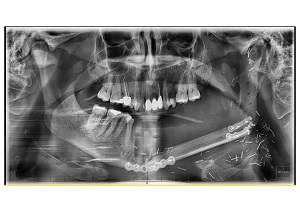

The ‘face-off’ surgery involved cutting out more than half of Paul O’Connor’s lower jaw and then reconstructing his face with bone taken from his leg.

“To ensure we successfully removed the cancer, we had to take out most of his lower jaw,” Dr Birch said.

A piece of bone from Mr O’Connor’s leg was then used to reconstruct the jaw. Dr Birch said Mr O’Connor‘s recovery was incredible but it had been a long road to recovery.